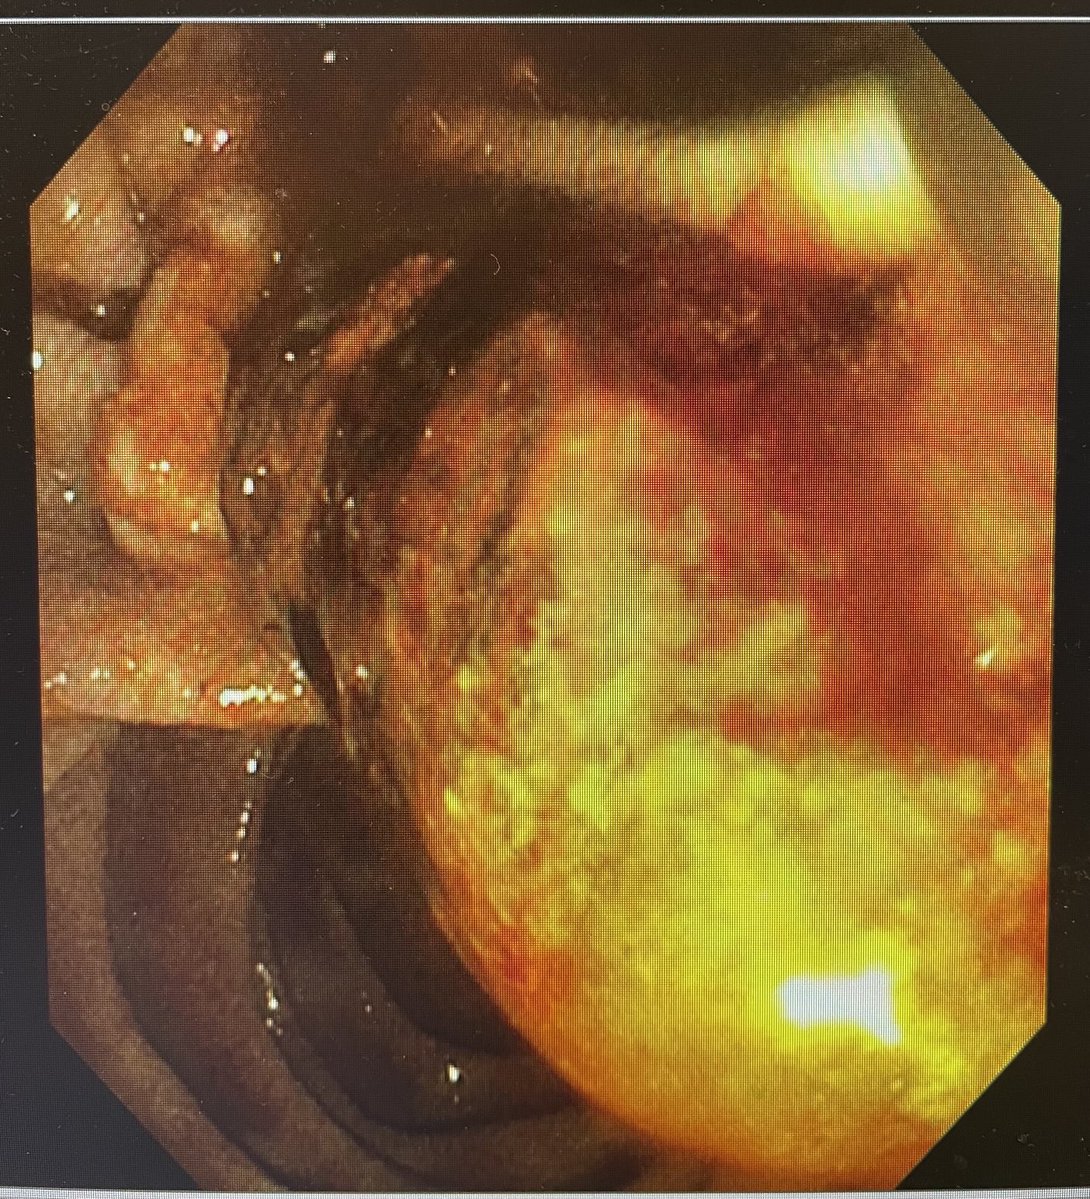

⚡️Tips to improve lift for resection⚡️

1. SSLs: No injection if margins are visible or < 20 mm

2. 10-30 mm lesions: central injection

3. Dominant lesions: start from accessible region

4. >30: inject, cut, repeat